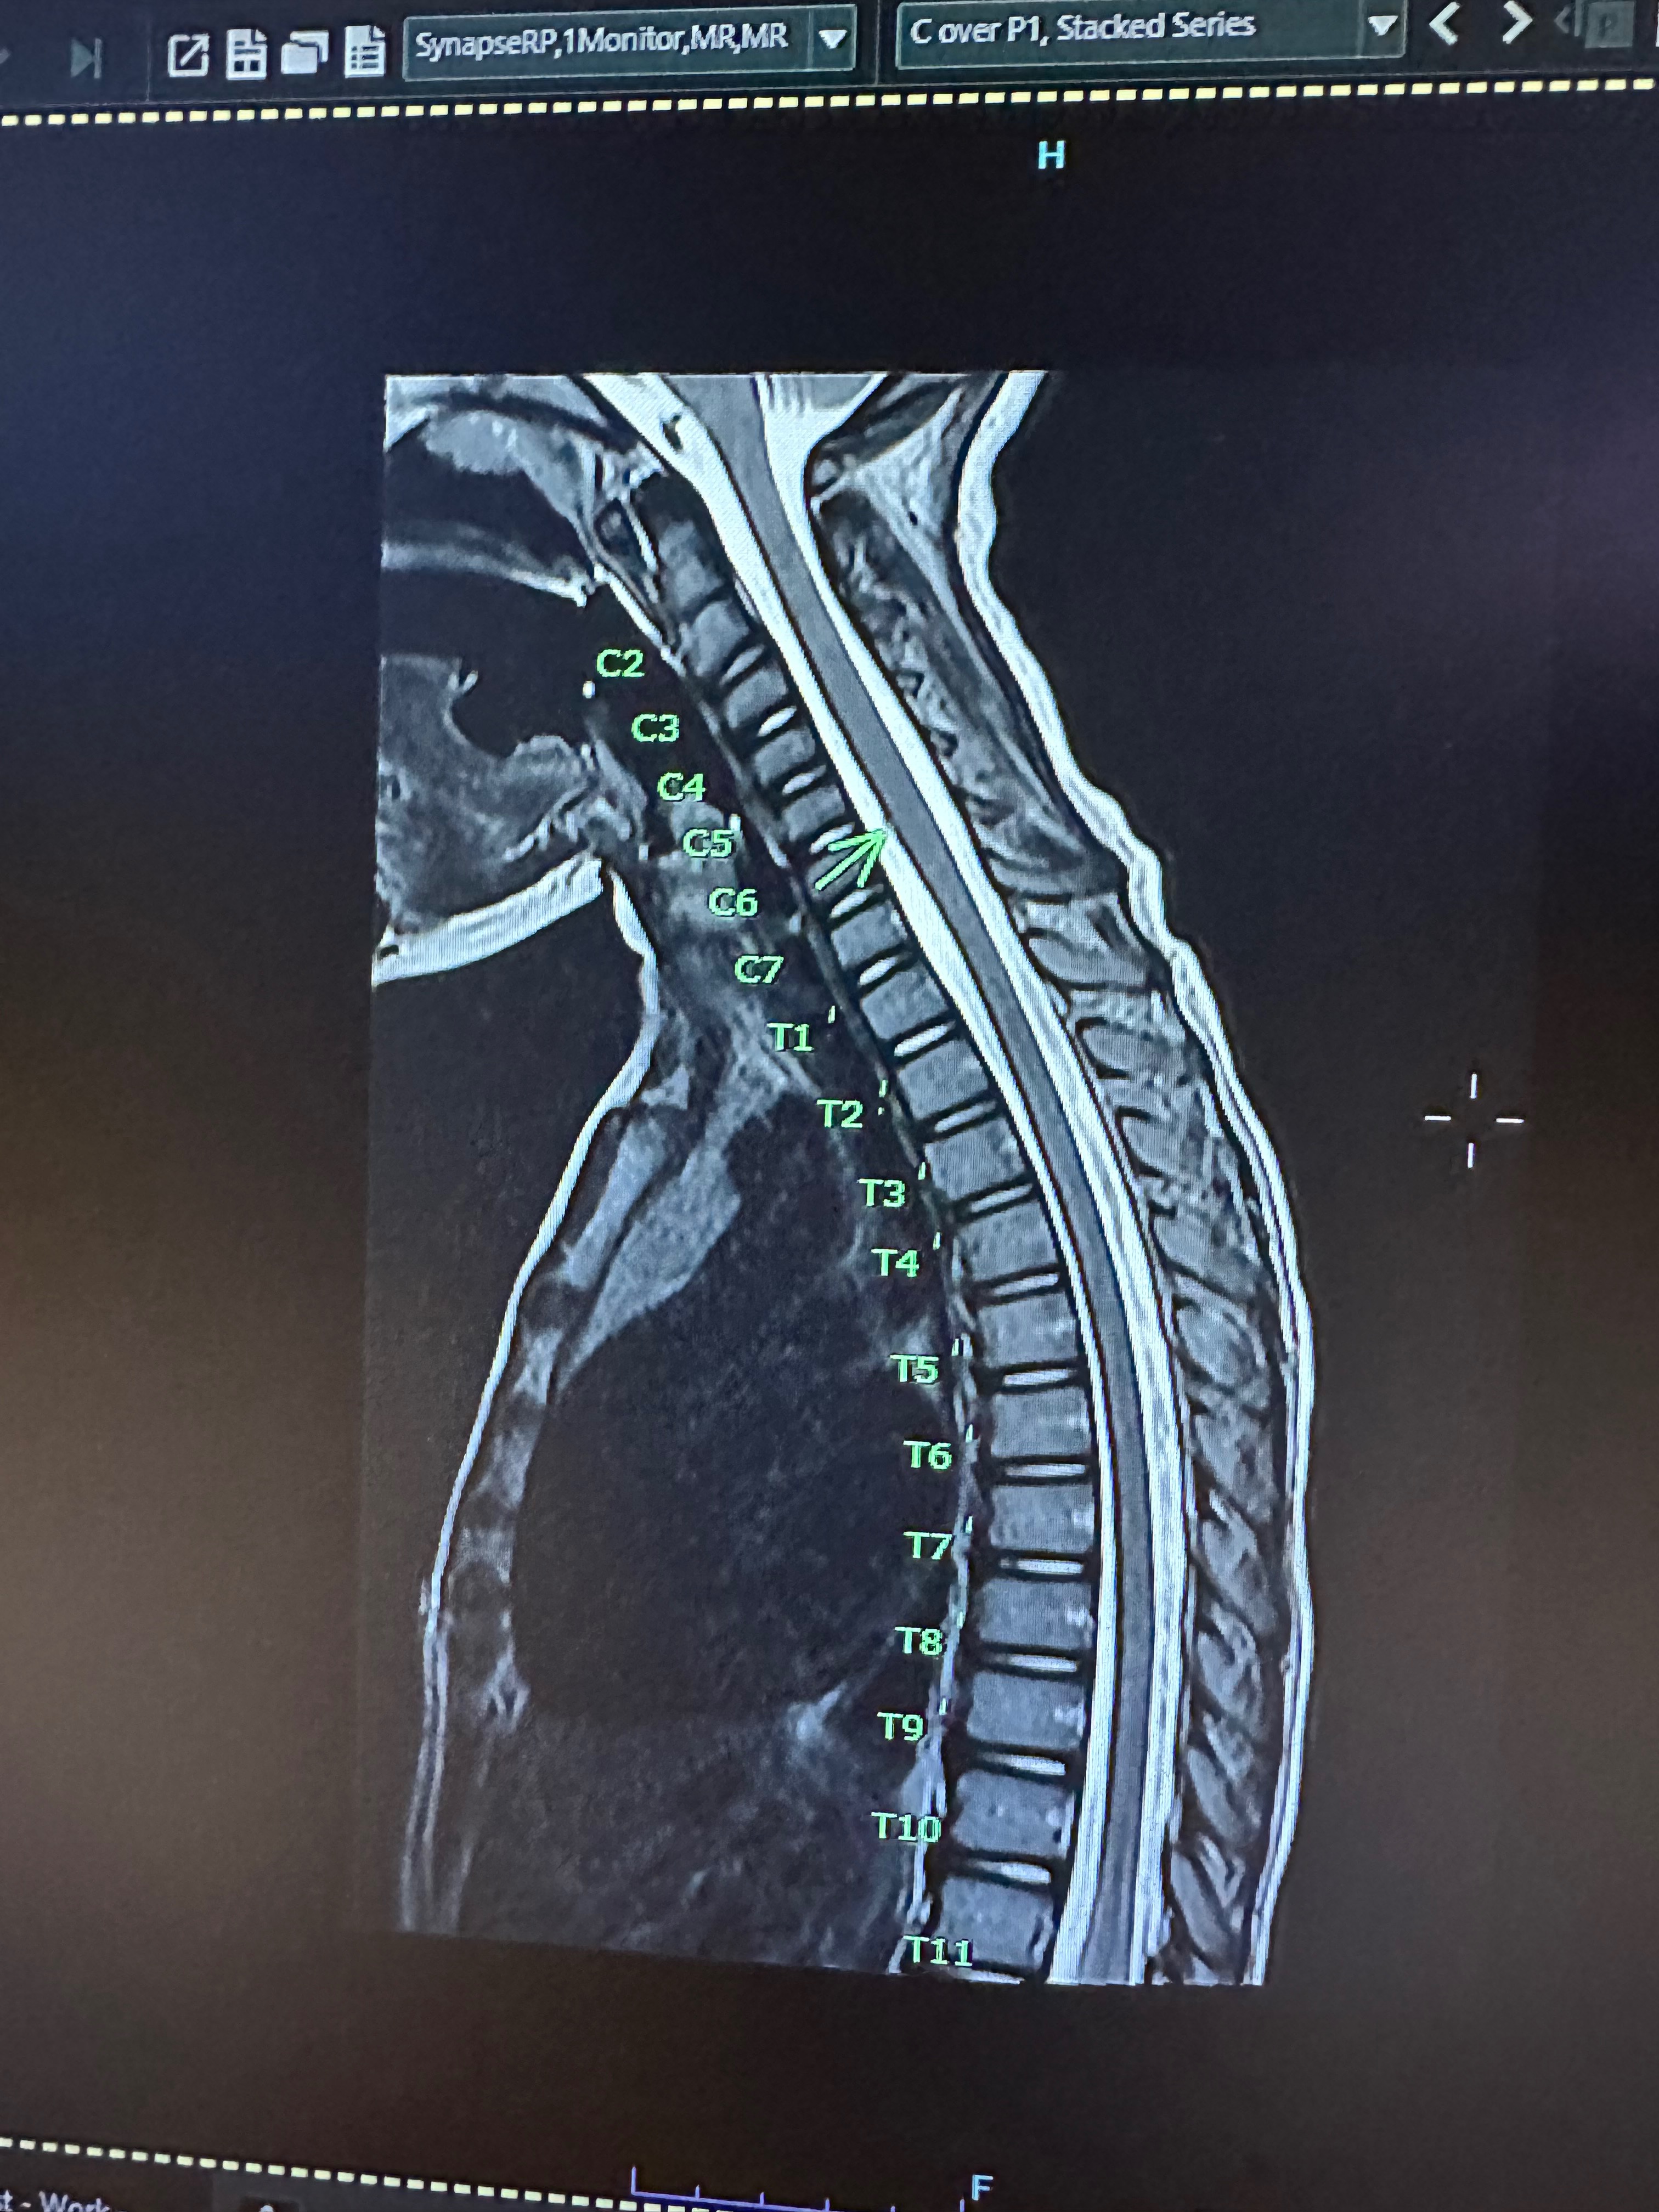

Her second hospitalization began on November 25, and a new MRI showed that the main tumor had grown, multiple new small lesions had appeared in her brain, and tiny spots were also seen on her spine. Part of the tumor presses near the areas of the brain that control vision and body functions, and another part sits on her medulla, likely causing her constant nausea.